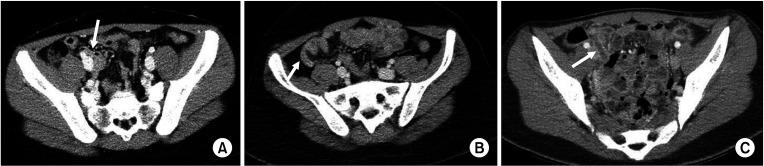

Patients younger than 19 years who visited Seoul National University Bundang Hospital with a differential diagnosis of appendicitis from January 2013 to December 2017 were included. All participants conducted 'appendiceal CT' with a scoring scale of 1-5. The higher the score, the higher the likelihood of a radiologic diagnosis of appendicitis. We defined the appendicitis CT score of 2-4 as equivocal appendicitis (n = 143). Medical records were reviewed retrospectively for demographics, further examination as abdominal ultrasonography, and appendectomy status (yes or no). The mean follow-up period was 15.6 ± 71 days.

Equivocal appendicitis accounted for 16.7%. Additional ultrasonography test was performed in 24.5% (35 of 143). In total, 34 patients (23.8%) underwent appendectomy. Among the patients with appendiceal CT scores 2, 3, and 4, 4.9%, 50.0%, and 87.5% underwent appendectomy, respectively. Higher WBC count, higher appendicitis CT score, and readmission were significantly associated with appendectomy in patients with equivocal appendicitis.

Higher appendicitis CT score and WBC level were positively associated with appendectomy. Careful observation can be a treatment option in appendicitis CT score 2 or 3 groups. Appendectomy is the first-line treatment for patients with appendicitis score 4. Additional ultrasonography test is advisable to determine treatment modality for equivocal appendicitis.